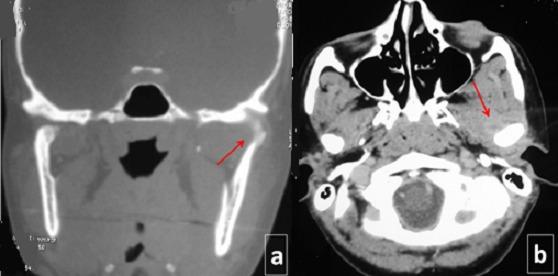

颞下颌关节双侧化脓性关节炎:病例报告

Bilateral septic arthritis of the temporo mandibular joint: case report.

Septic arthritis of the temporo-mandibular joint (TMJ) is a rare disease that has been reported infrequently. To the best of the authors' knowledge, only one case of bilateral TMJ septic arthritis has been reported. The contamination may result from direct extension of adjacent infection (dental or ENT), from hematogenous spread of blood-borne organisms or from direct inoculation. The most common presenting are trismus and pain, although swelling, tenderness and erythema have also been described. In addition, patients may develop fever, regional lymphadenopathy and malocclusion. Through a successively bilateral case of TMJ arthritis, without obvious portal of entry of the bacteria, we will analyze characteristics and treatment of this disease.

颞下颌关节(TMJ)化脓性关节炎是一种罕见疾病,鲜有报道。据作者所知,仅报告过一例双侧TMJ化脓性关节炎病例。感染可能源于邻近感染(牙科或耳鼻喉科)的直接蔓延、血行性生物体的血行播散或直接接种。最常见的症状是牙关紧闭和疼痛,不过也有肿胀、压痛和红斑的描述。此外,患者可能会出现发热、局部淋巴结病和错牙合畸形。通过一例连续双侧TMJ关节炎病例,在无明显细菌入口的情况下,我们将分析该疾病的特征及治疗方法。